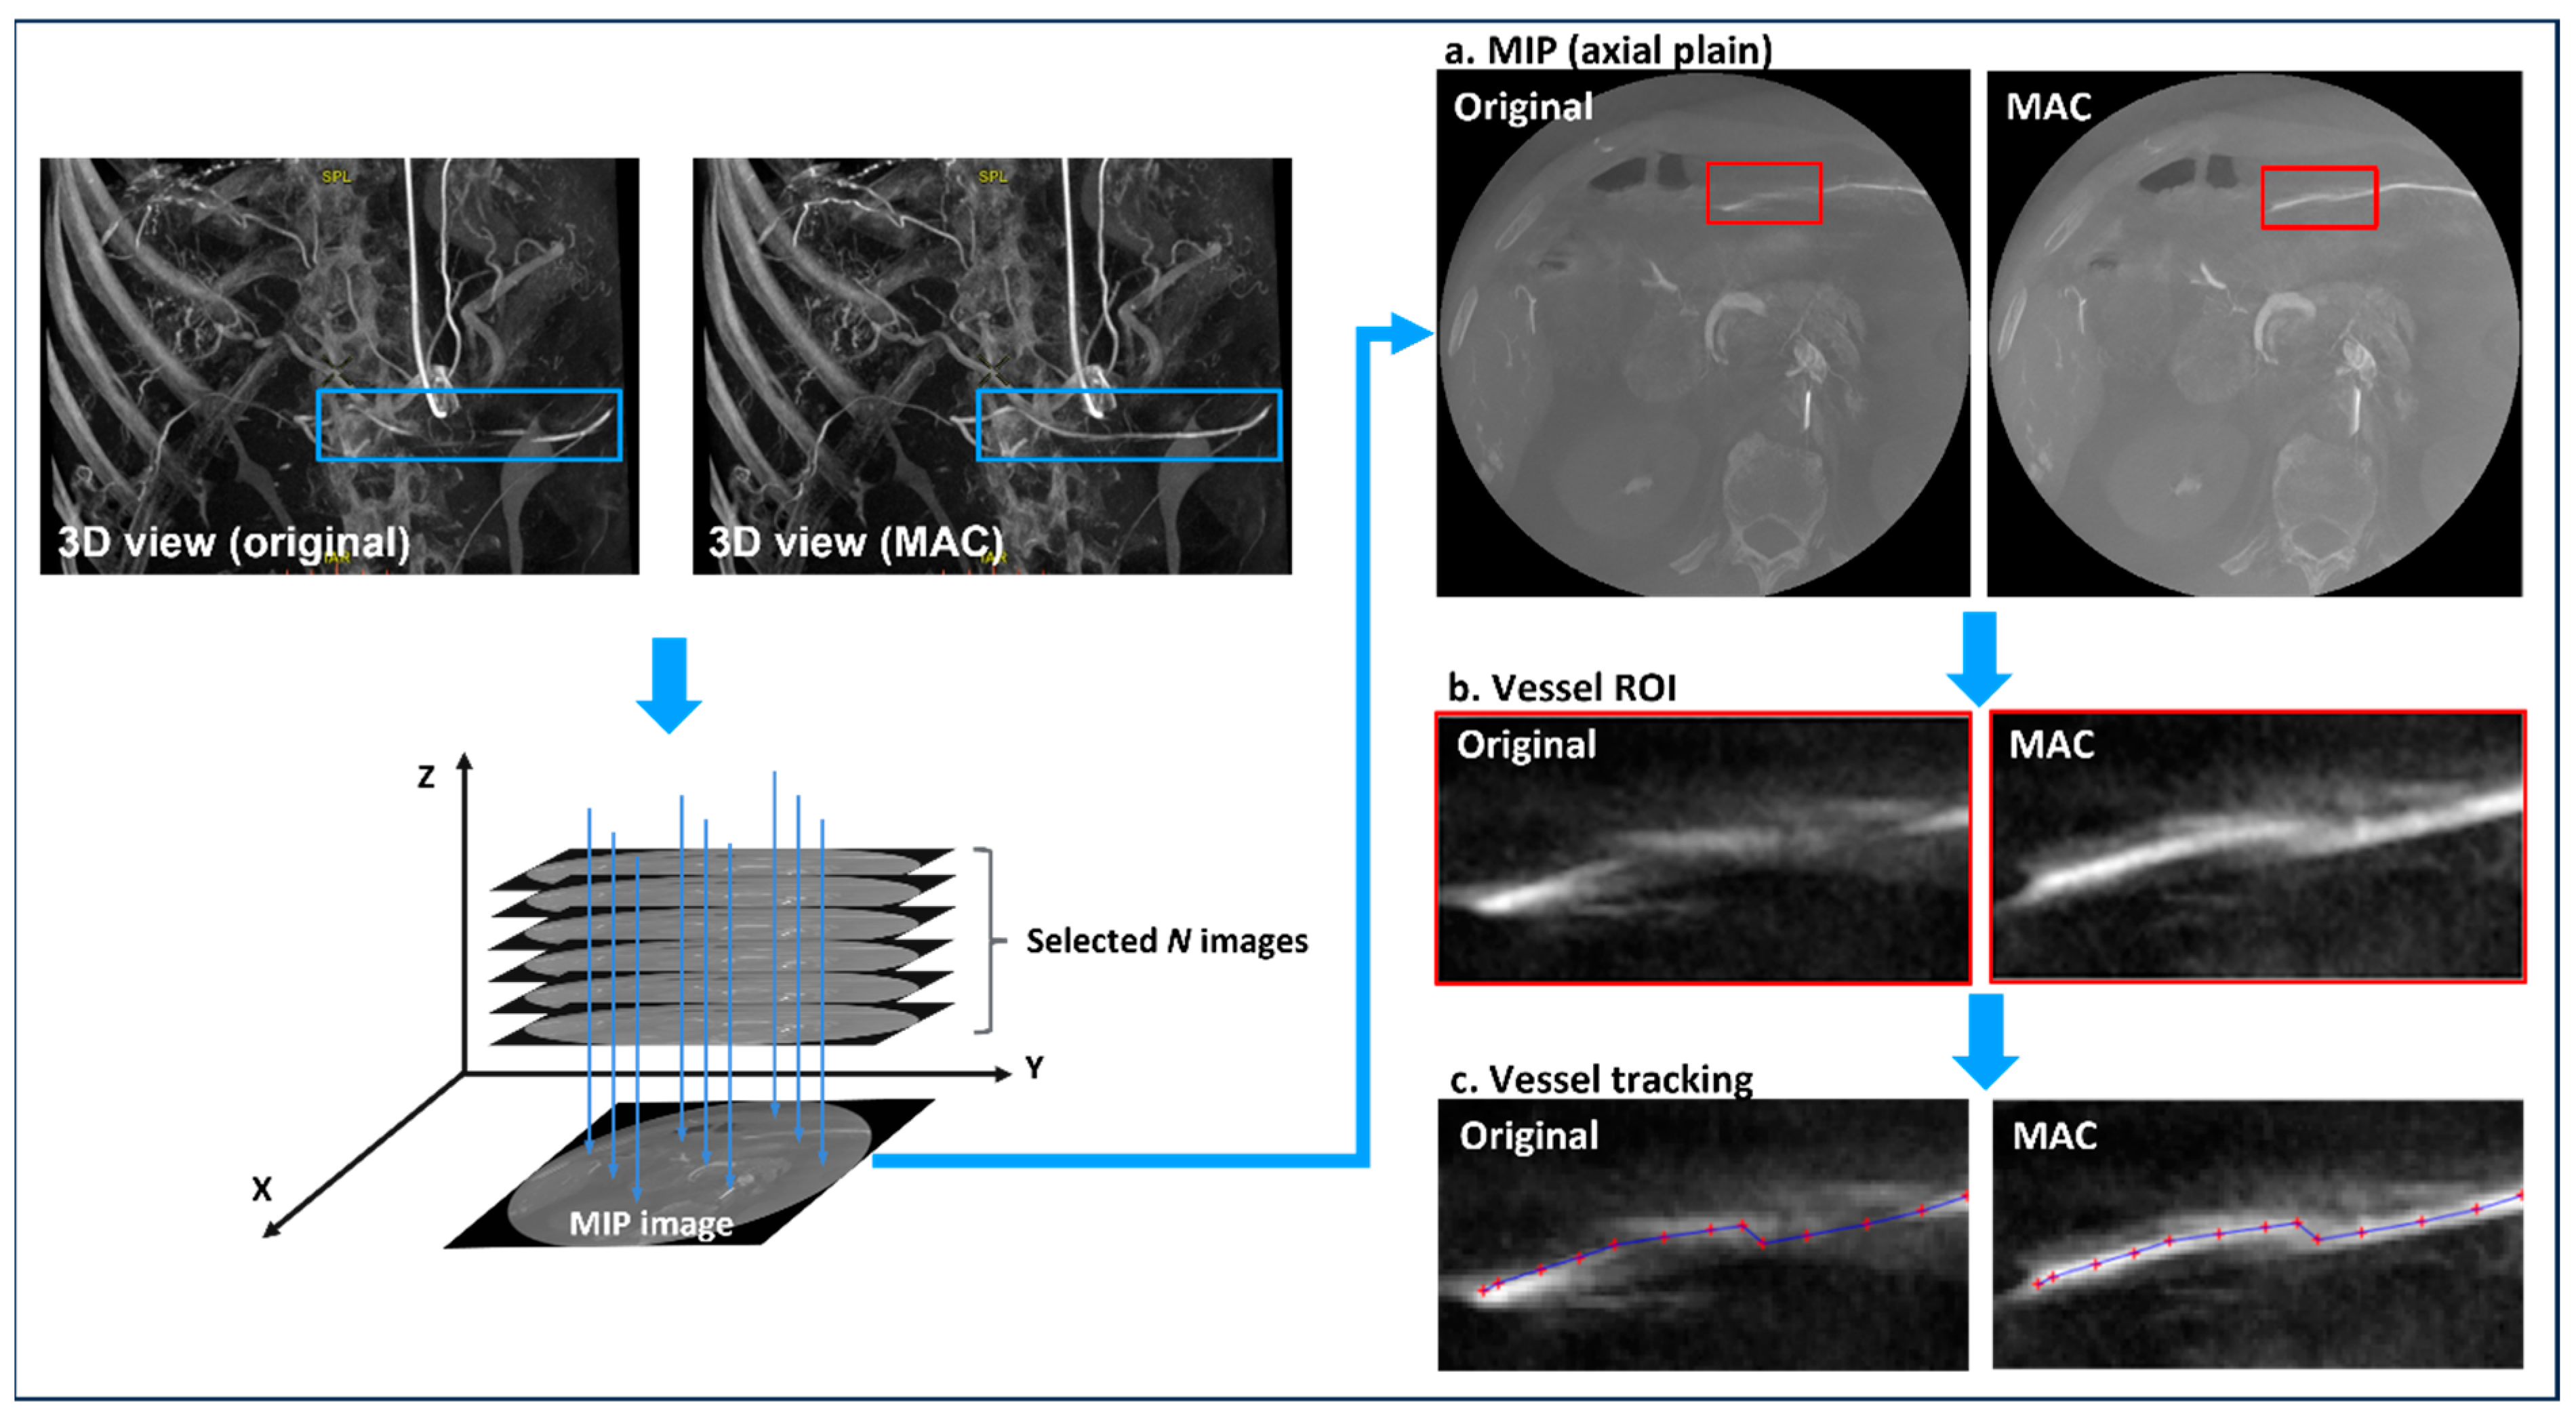

2.2. Motion-Corrected Index

2.3. Experiment 1

2.4. Experiment 2